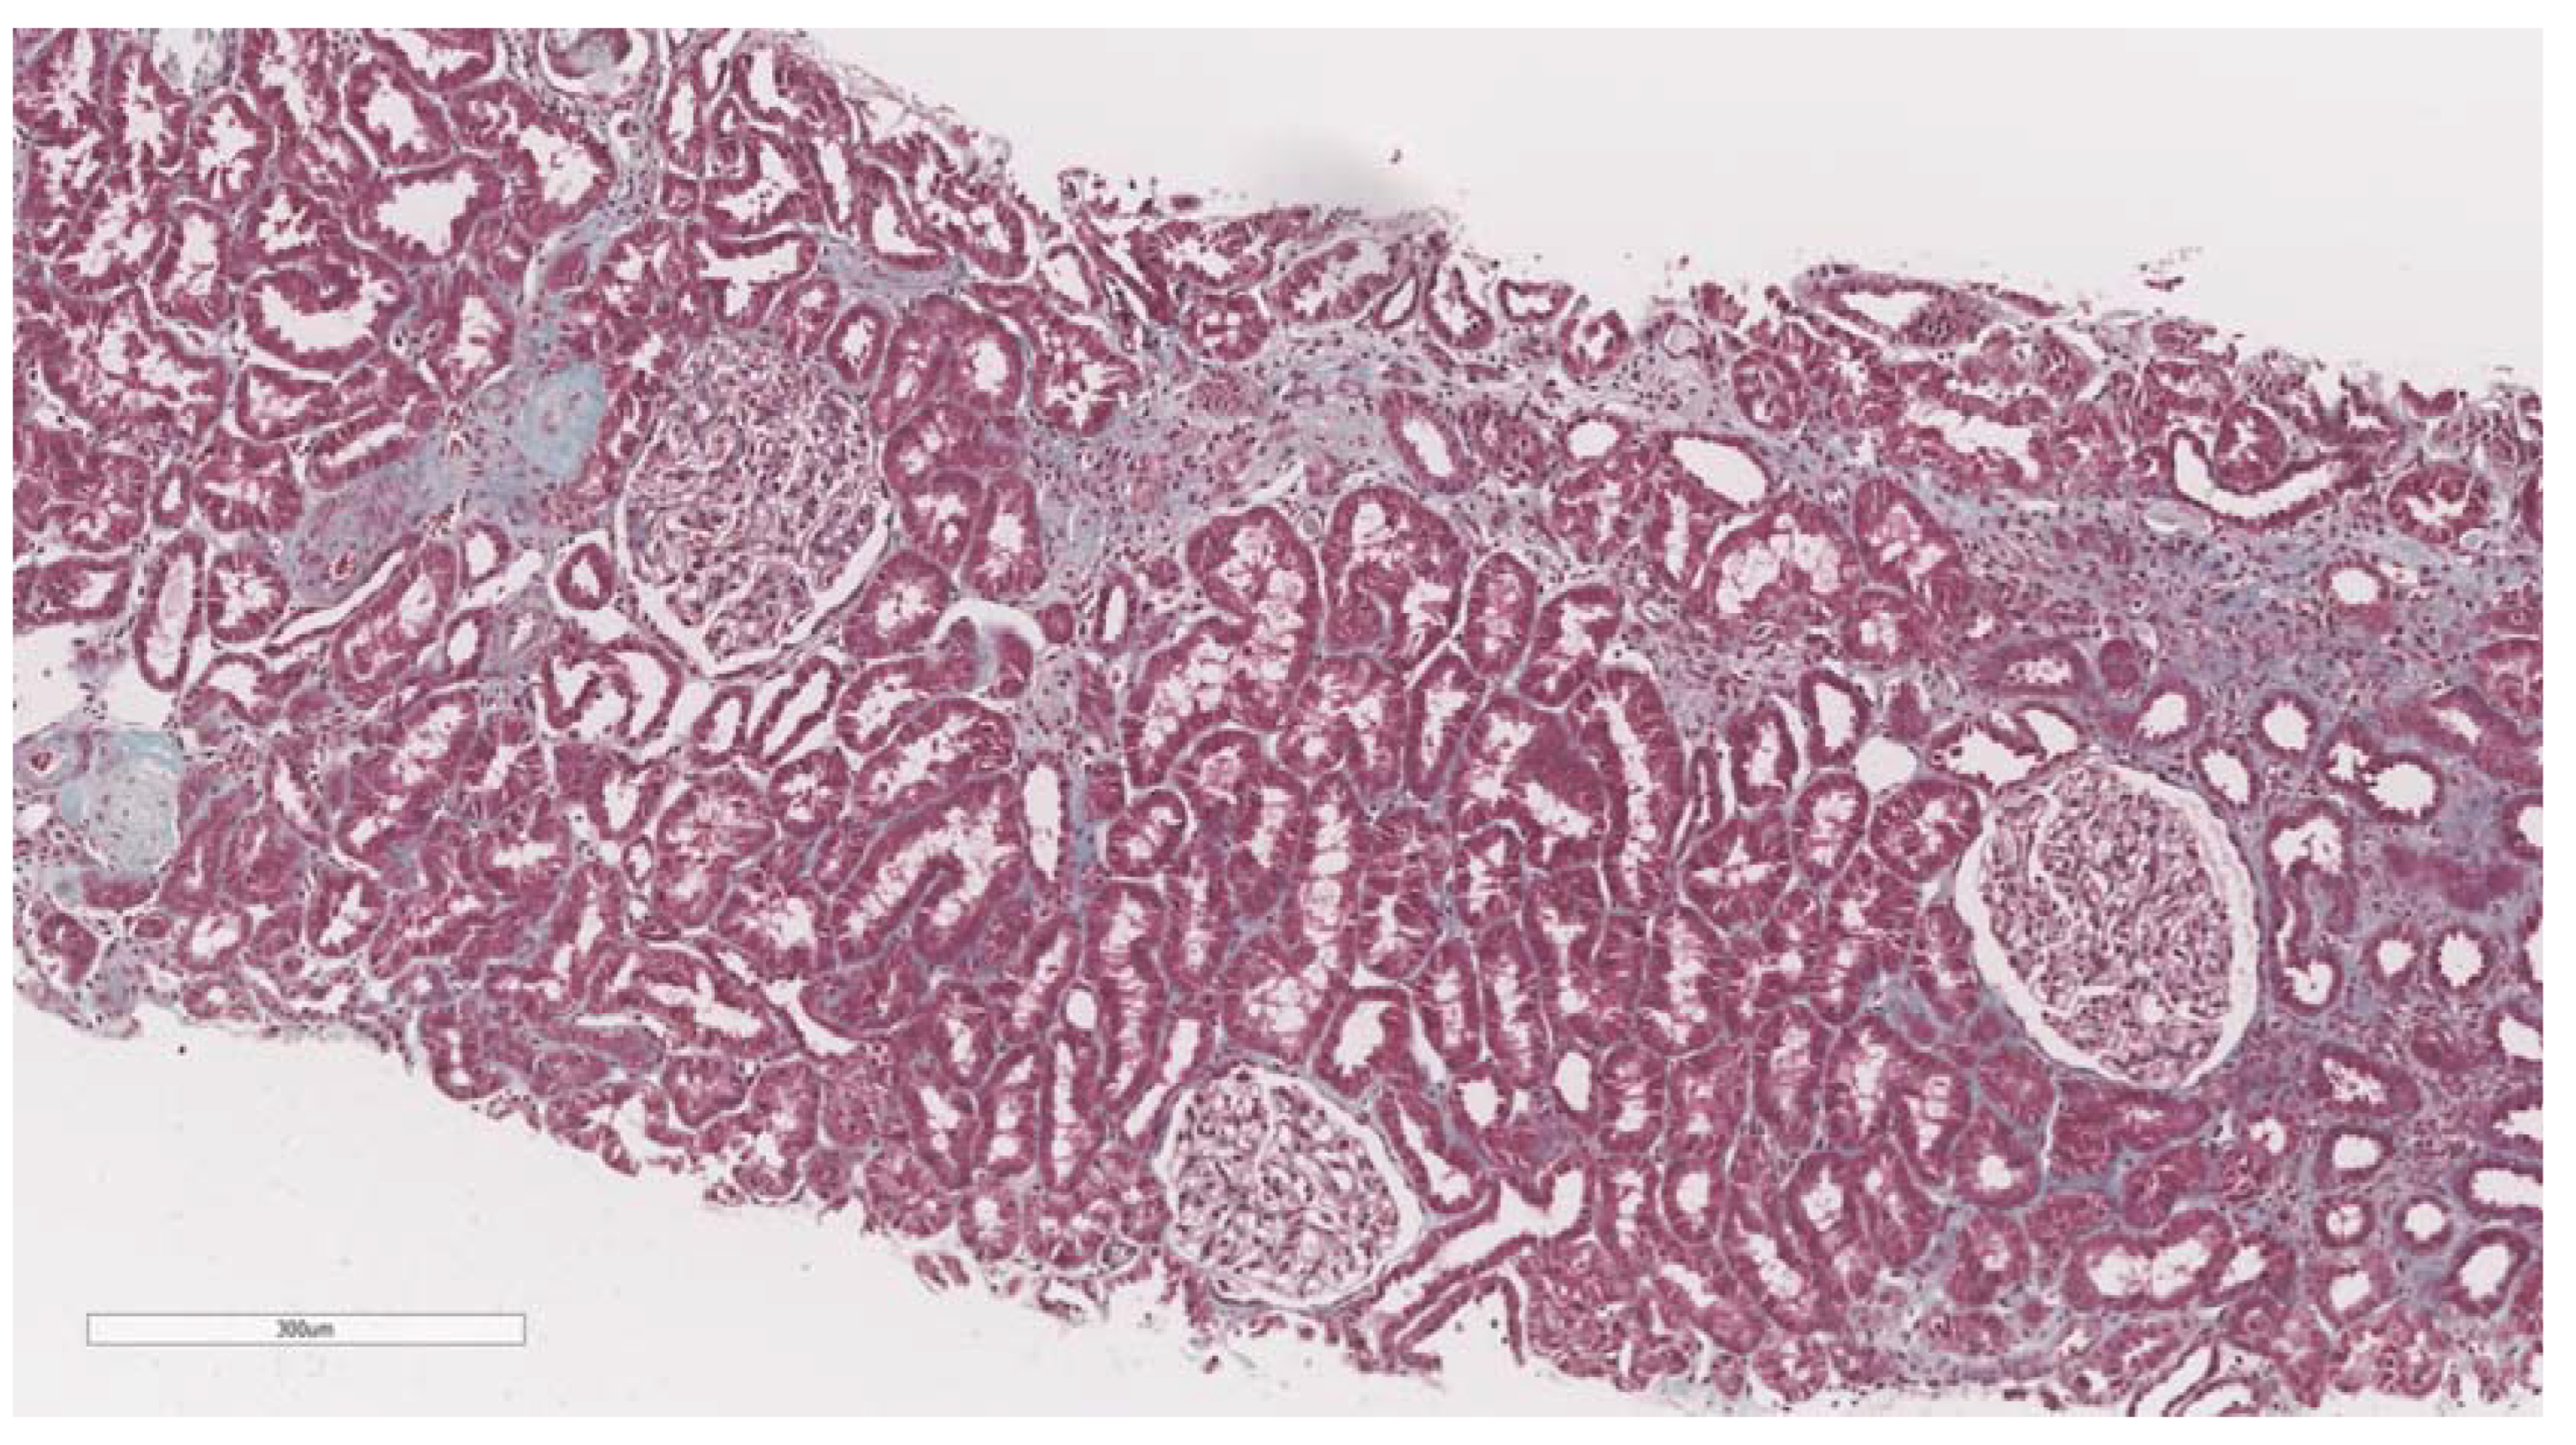

2.3. Renal Biopsy and Histopathology

- Haas, M.; Seshan, S.V.; Barisoni, L.; Amann, K.; Bajema, I.M.; Becker, J.U.; Joh, K.; Ljubanovic, D.; Roberts, I.S.; Roelofs, J.J.; et al. Consensus definitions for glomerular lesions by light and electron microscopy: Recommendations from a working group of the Renal Pathology Society. Kidney Int. 2020, 98, 1120–1134. [Google Scholar] [CrossRef]